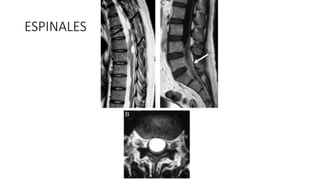

ESPINALES

• #39 Afectación espinal por cisticercosis. Estudio de RM mediante secuencias potenciadas en T2 en el plano sagital de la columna dorsal (A), T2 axial de la columna lumbar (B) y T1 sagi- tal con gadolinio de la columna lumbar (C), con múltiples quistes de diferentes tama˜nos, intradurales, intramedulares y extrame- dulares (flechas), que se localizan a lo largo del canal raquídeo en su segmento dorsal-lumbar, con reacción inflamatoria lepto- meníngea asociada (flecha).